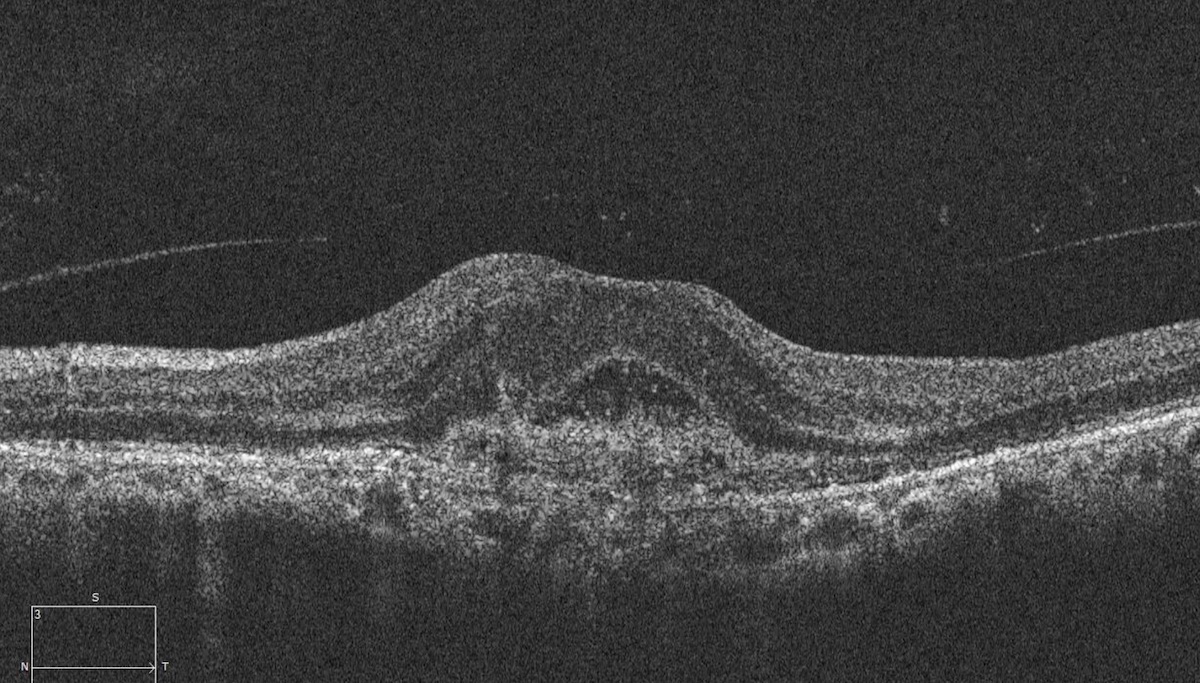

Here there is loss of the regular macular depression. There is a bright line present on the surface of the retina. In addition, there is separation of the retinal layers in the inner retina.

The patient was diagnosed with a schisis secondary to an epiretinal membrane. This complication is seen in over 50% of ERMs (video).

In any patient with intraretinal fluid consider the possibility of an epiretinal membrane causing a schisis.